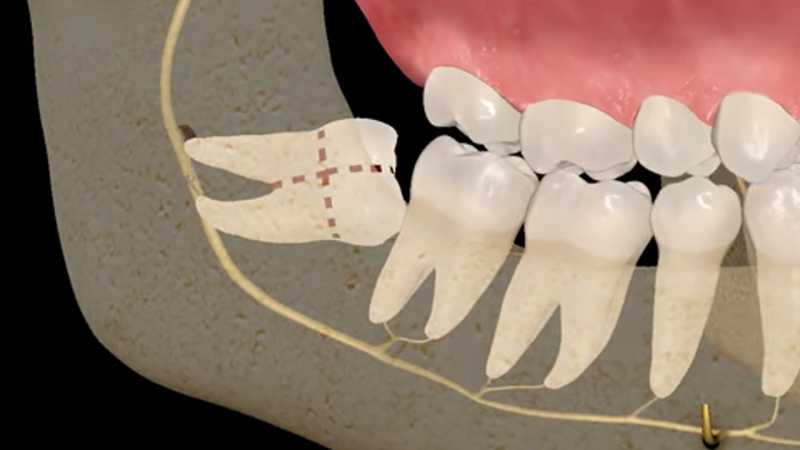

Inicio Especialidades Cirurgia